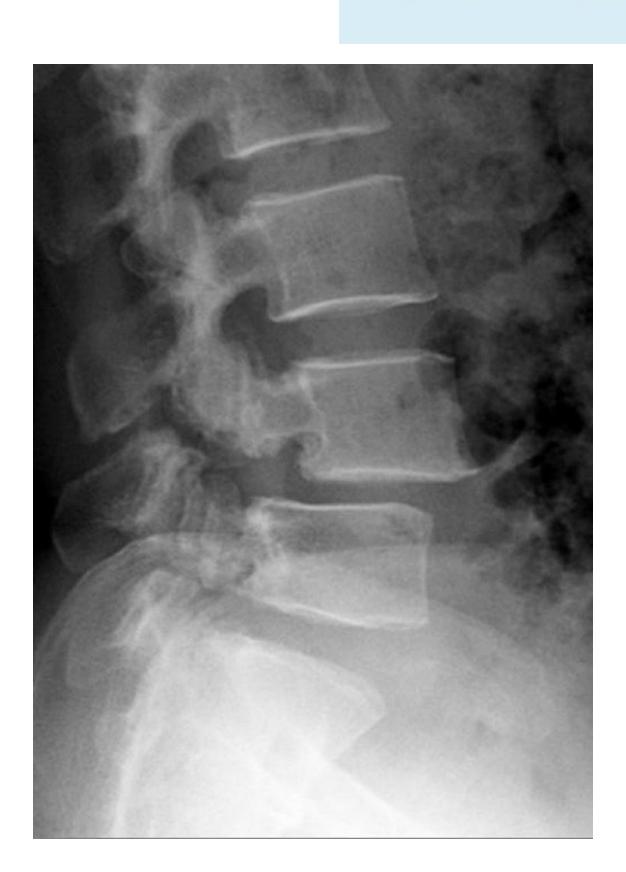

Back ROM & Neurological

This patient has back pain radiating down to his right leg. examine the back

| Move | General Motion Assessment | Change of shape/deformity during motion, Smoothness of motion, Extent (Range) | ![]() |

| Specific Movements | |||

| Flexion and Extension | ![]() | ||

| R and L lateral flexion | Sideway Bending | ![]() | |

| R and L rotation | Must be in Sitting position, help patient understand rotation movements | ![]() | |